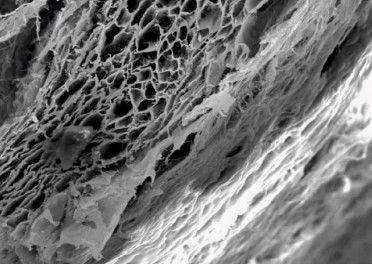

Resorbable collagen membrane has a unique bilayer structure that offers superior tissue compatibility and prevents the ingrowth of soft tissue into the augmented site. The membrane triggers the biological events for faster regeneration and gradually degrades itself. Collagen membrane is effective for dental bone graft applications.

Due to its porous and fibered microstructure, the membrane readily absorbs fluids, adheres to the surrounding tissues, and provides a barrier that guides bone and tissue regeneration.